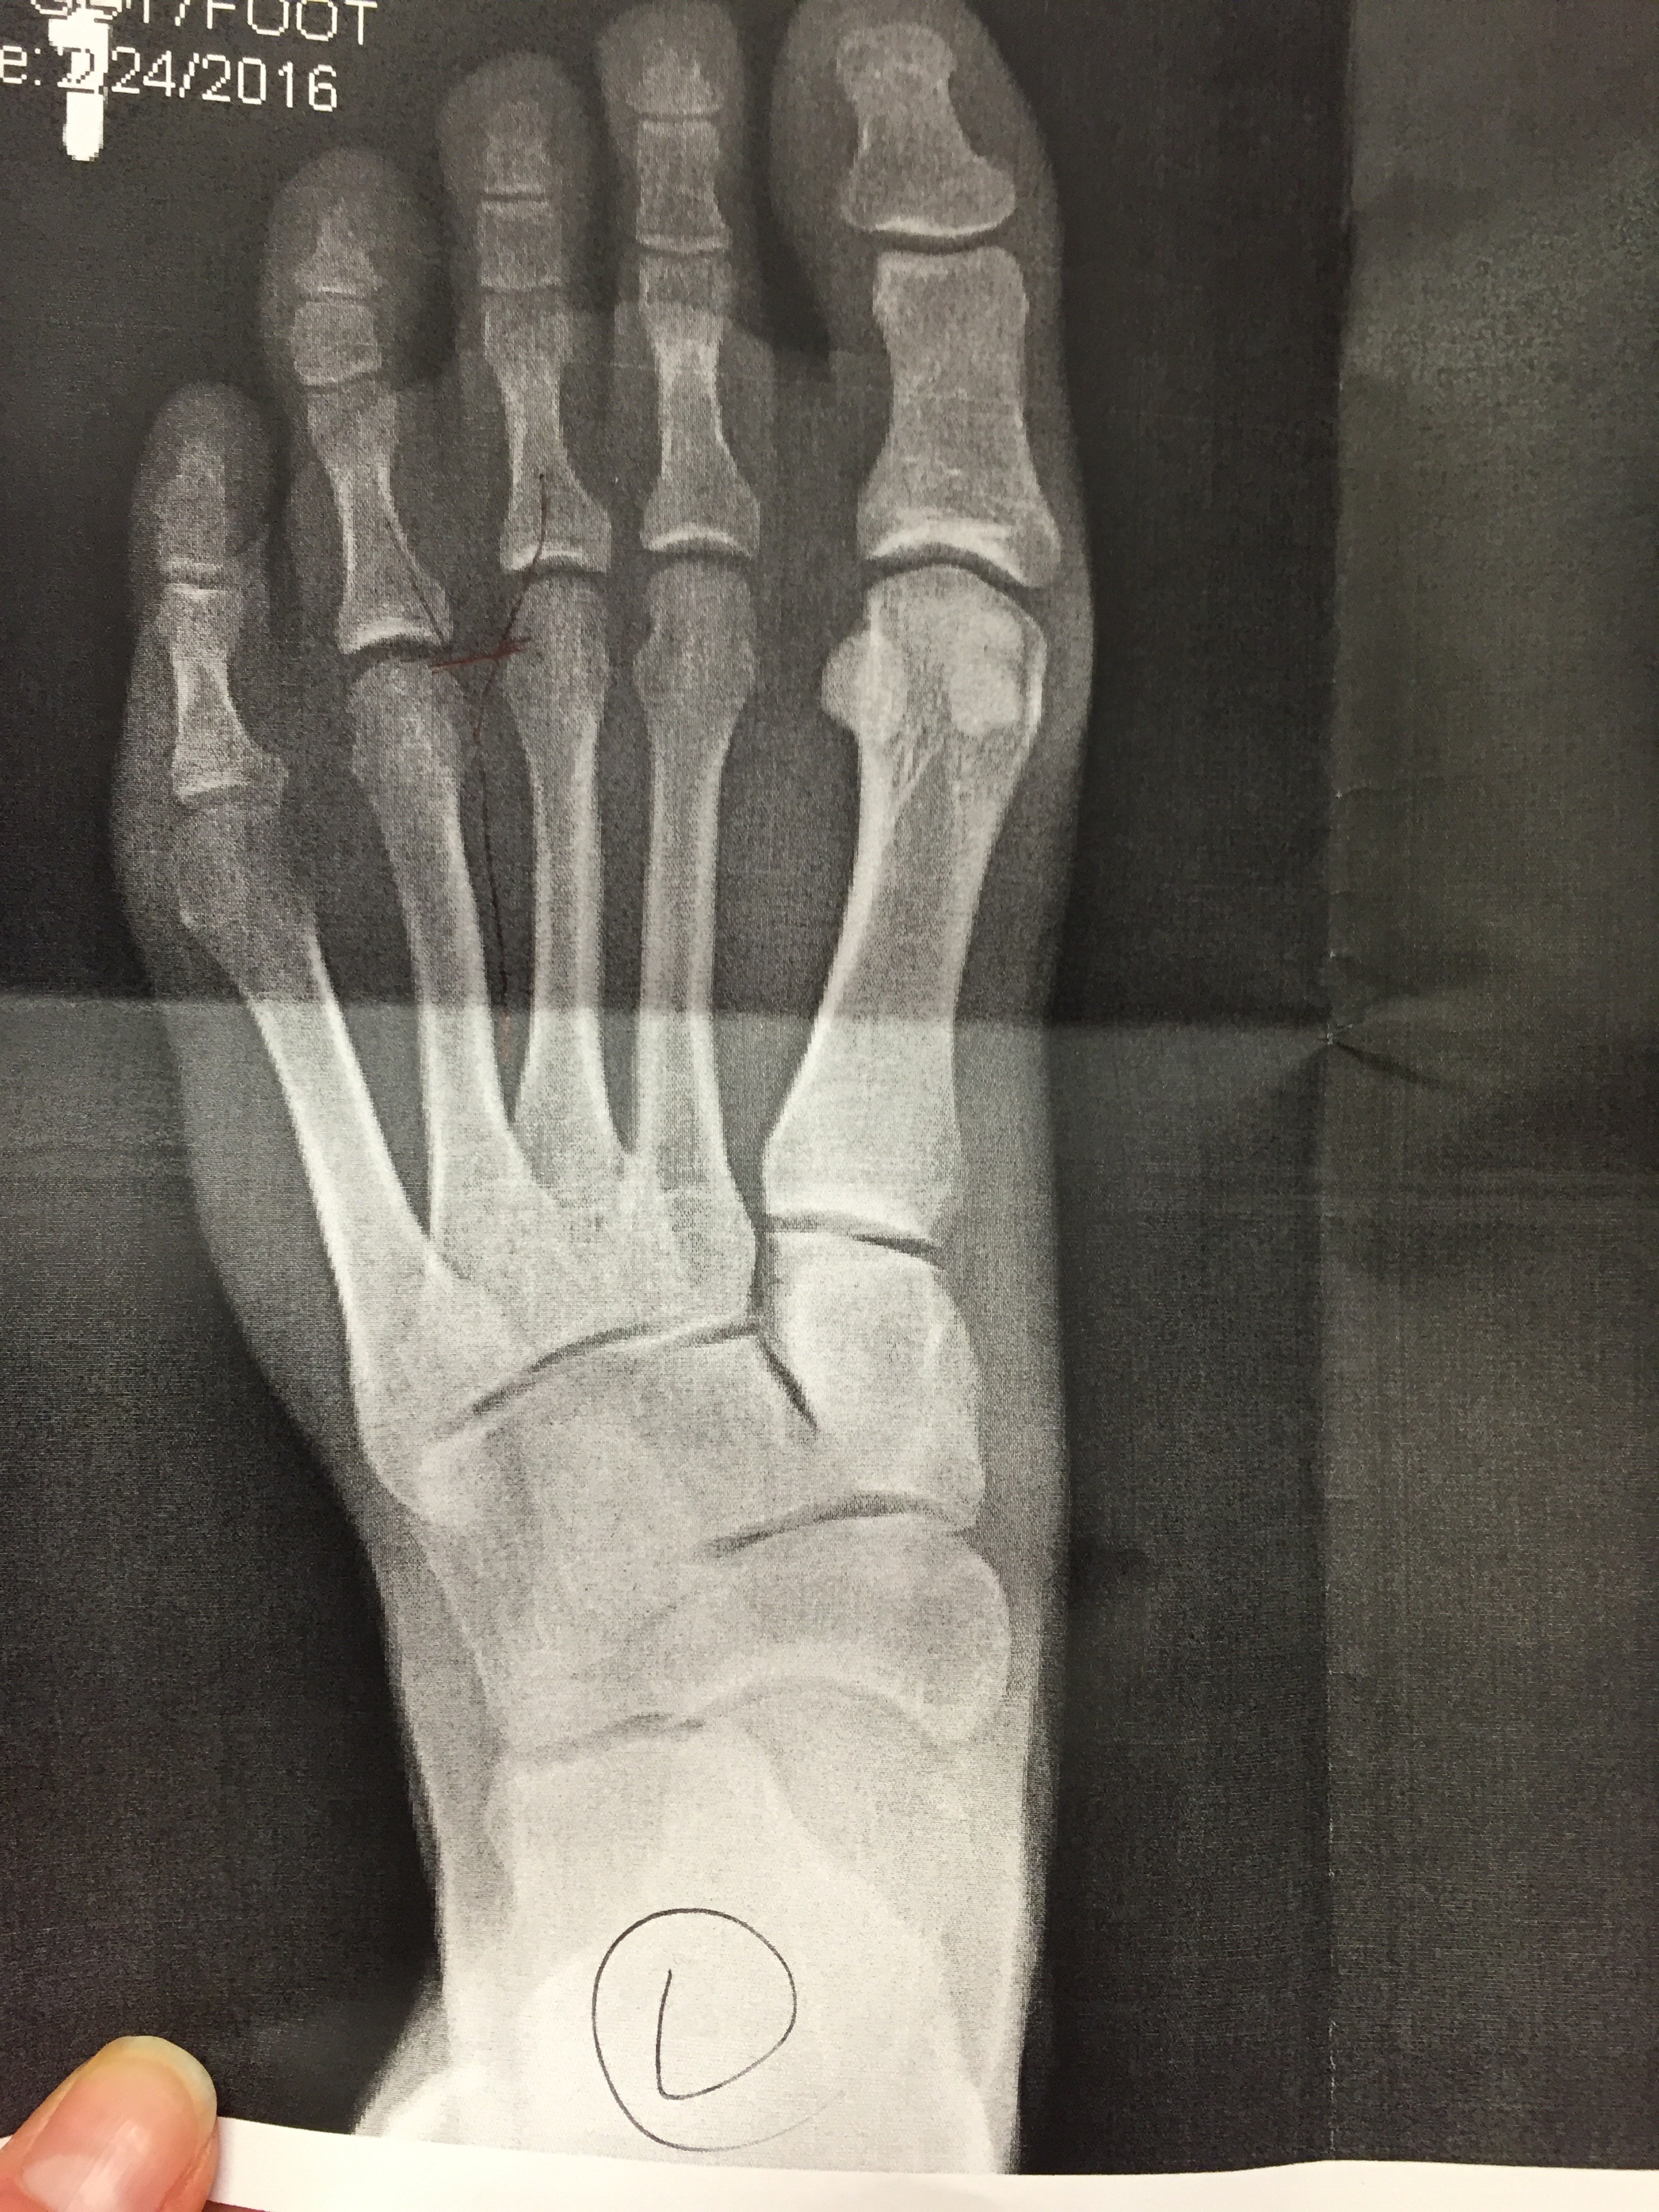

Mine was definitely a mild case, as I wasn’t experiencing any numbness or tingling. There was just pain that would get worse with activity. I went to the orthopedist to make sure I didn’t have any fractures and his advice was to lay off all activity for a while. He didn’t seem to think anything of the fact that by the time I went to see him my foot had already been hurting for 6 weeks. He offered me a cortisone shot, which I declined, and said to give it another 6 weeks.Foot injuries are the worst. Feet are needed to do everything!